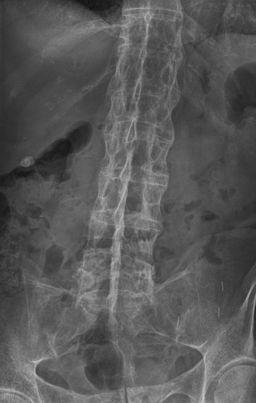

Las radiografías son la modalidad de imagen más útil en la enfermedad establecida, aunque pueden ser normales en la enfermedad temprana.

Busque una sacroileítis o una entesitis (en particular del anillo fibroso). La sacroileítis se manifiesta inicialmente como una borrosidad en la parte inferior de la articulación, después se producen erosiones óseas o esclerosis y ensanchamiento o fusión eventual de la articulación.

Los cuerpos vertebrales pueden volverse "cuadrados". En etapas posteriores, se forman puentes óseos (sindesmofitos) entre las vértebras adyacentes, hay osificación de los ligamentos espinales y, en la fase avanzada de la enfermedad, puede haber fusión completa de la columna vertebral (columna de bambú).

La osteopenia espinal es frecuente.

Lomo de bambú

Por Stevenfruitsmaak, vía Wikimedia Commons